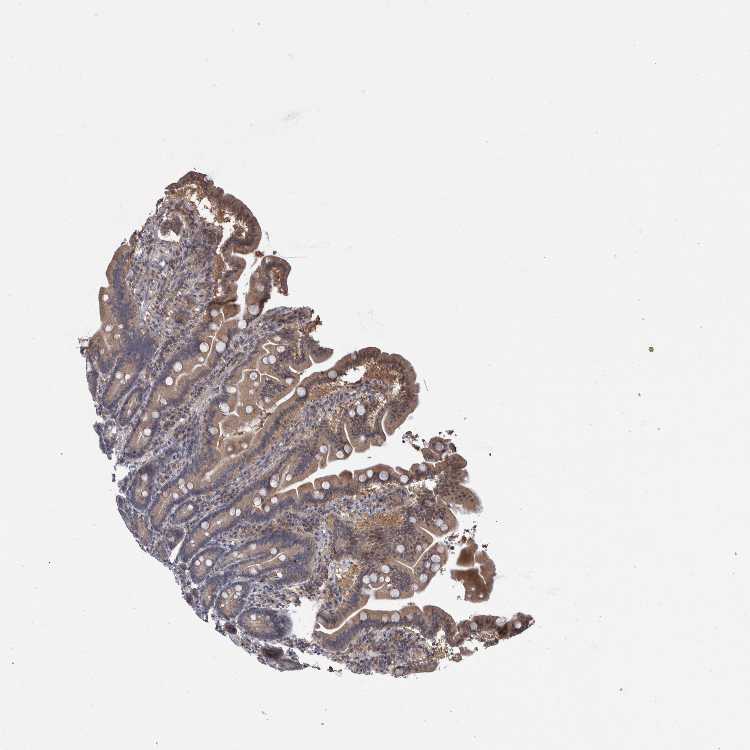

DUODENUM

Tissue proteome

Intestine